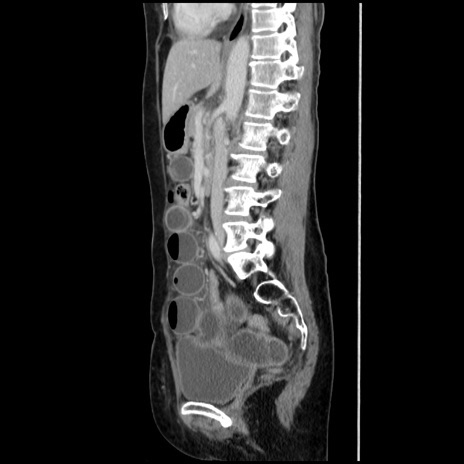

症例32(矢状断像)

横断像